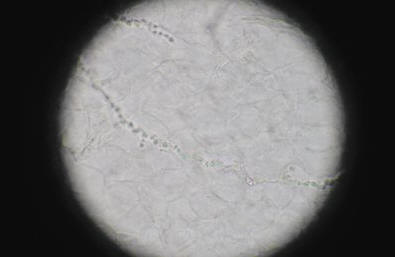

Микроскопия клинического материала — быстрый и простой метод предварительной диагностики заболевания. В случаях отсутствия роста возбудителя в культуре положительный результат прямой микроскопии может являться несомненным подтверждением микотической инфекции. В соскобах с кожи и ногтей дерматофиты, как правило, представлены тонким, диаметром 2–4 мкм, прямым и редко ветвящимся мицелием. Часто в препарате можно обнаружить атипичные формы мицелия дерматофитов — цепочки округлых артроспор (рис. 3).